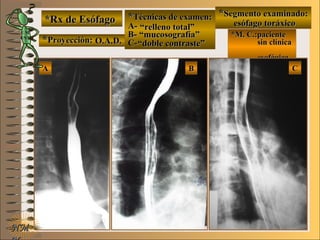

*Rx de Esófago*Rx de Esófago

**Proyección:Proyección:

**Técnicas de examen:Técnicas de examen:

A-A-

B-B-

C-C-

**Segmento examinado:Segmento examinado:

*M. C.:paciente*M. C.:paciente

sin clínicasin clínica

esofágicaesofágica

O.A.D.O.A.D.

““relleno total”relleno total”

““mucosografía”mucosografía”

““doble contraste”doble contraste”

esófago toráxicoesófago toráxico

A-A-El examen es normal o patológico?El examen es normal o patológico?

Examen normal de esófago toráxico con técni-Examen normal de esófago toráxico con técni-

cas de : A- relleno total, B- mucosografía (tienecas de : A- relleno total, B- mucosografía (tiene

por objetivo reconocer el relieve interno gruesopor objetivo reconocer el relieve interno grueso

= a pliegues) y C- doble contraste (relieve interno= a pliegues) y C- doble contraste (relieve interno

fino) en proyección O.A.D.fino) en proyección O.A.D.

B-B-Puede describir la o las imágenesPuede describir la o las imágenes

En estas radiografías en proyección O.A.D. seEn estas radiografías en proyección O.A.D. se

deben distinguir sobre el borde anterior de esófagodeben distinguir sobre el borde anterior de esófago

toráxico tres “muescas”, arcos o compresionestoráxico tres “muescas”, arcos o compresiones

determinadas de craneal a caudal por: 1- botóndeterminadas de craneal a caudal por: 1- botón

aórtico, 2- bronquio fuente izquierdo y 3- aurículaaórtico, 2- bronquio fuente izquierdo y 3- aurícula

izquierdaizquierda